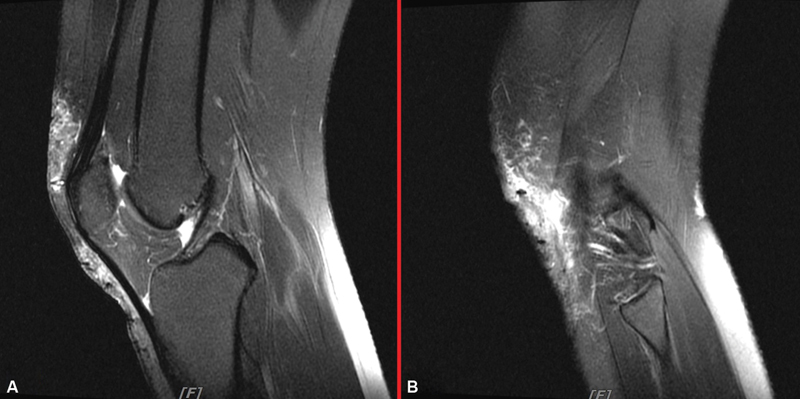

Abstract Image